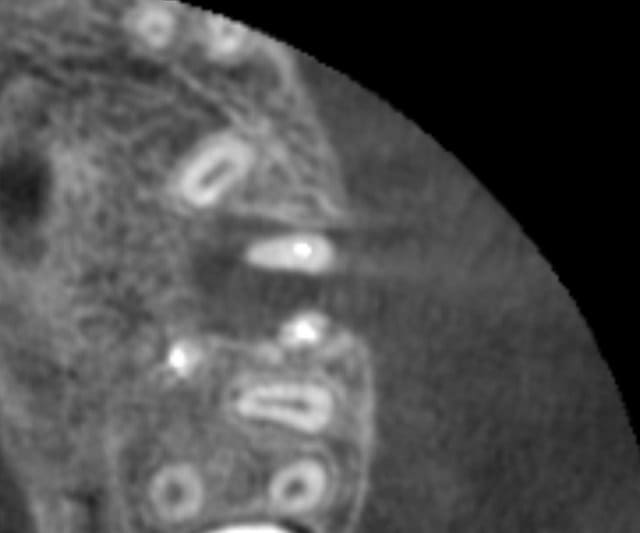

Ok, donc 2 autres coupes axiales:

Mais au bout d'un moment la 3 d montre pas tout: tu peux ne pas voir une lumiere canalaire qui existe dans la dent.

+ l'artefact du gros cone de gutta

(j'ai mis 2 fois la meme : arrive pas à la retirer)

sur la 4ème coupe, on voit que l'endo du canal palatin n'est pas top. tu as repris tous les canaux ou uniquement les mvs?

ton canal mésio ves avec commnunication MV1 MV2 est de forme

allongée comme sur la 27 et ton cône de gutta est central

et n'obture pas tout l'apex de façon hermétique (par contre

"bonjour la difficulté d'obturation 3d mac spadden ou système B?)

tout ceci ce sont des interprétations et je pense que le bout de l'apex mésio ves de ta 26 est allongé ;c'est pourquoi on réclame plus de coupes CBCT possible puisque tous les mm et en particulier la coupe du bout des 3 apexs

de ta 26